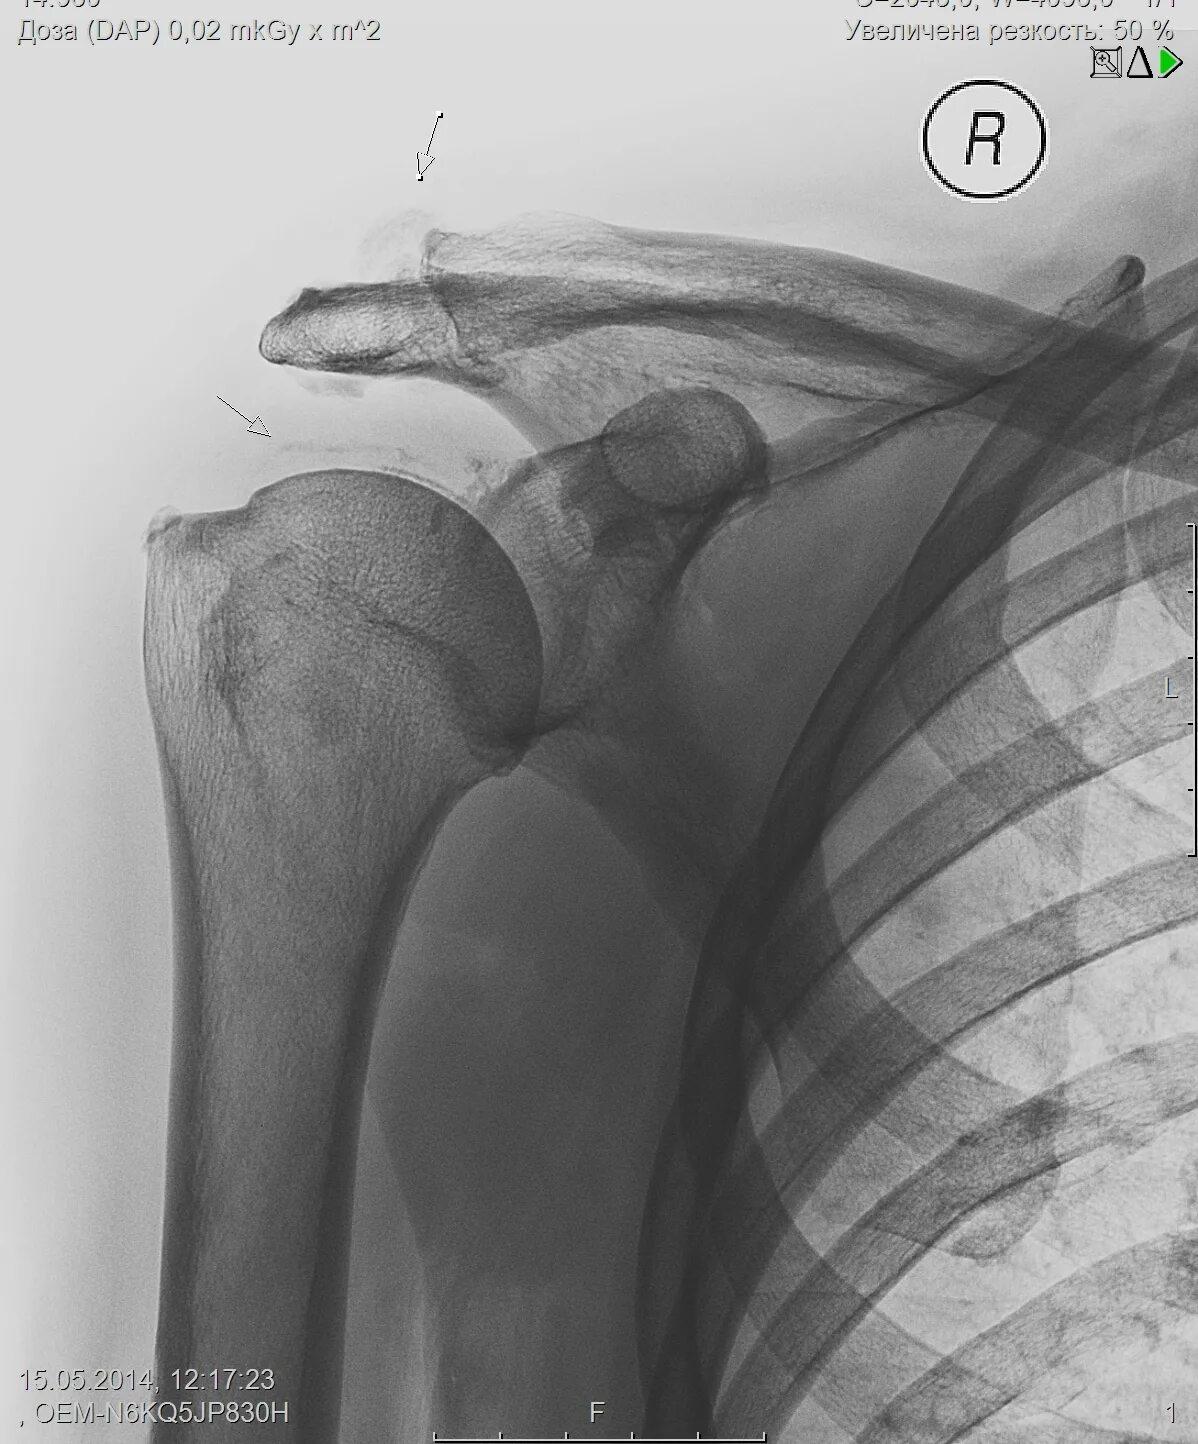

Обызвествление сухожилий мышц